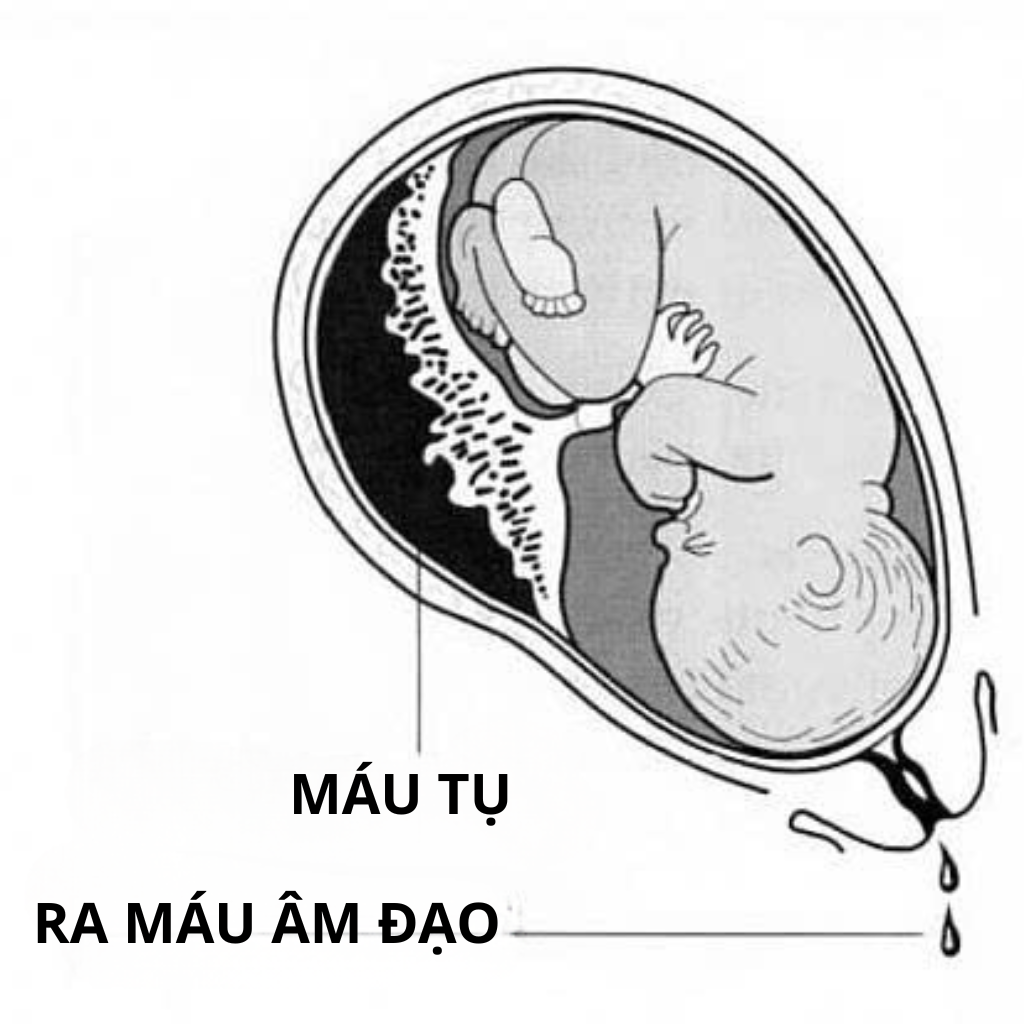

Nhau bong non là tình trạng bánh nhau tách khỏi thành tử cung trước khi thai được sinh ra.

Trong thai kỳ bình thường, bánh nhau bám chắc vào thành tử cung để cung cấp oxy và dưỡng chất cho thai. Khi xảy ra nhau bong non:

- Một phần hoặc toàn bộ bánh nhau bị bong

- Máu có thể tụ phía sau bánh nhau

- Dòng máu nuôi thai bị gián đoạn

- Thai có nguy cơ thiếu oxy

Vì sao ra máu ít vẫn có thể nguy hiểm?

Một sai lầm phổ biến là nghĩ rằng máu ít thì không nghiêm trọng.

Trong nhau bong non:

- Máu có thể tụ phía sau bánh nhau

- Lượng máu ra ngoài không phản ánh mức độ thực sự

- Thai có thể thiếu oxy dù chảy máu ít

Vì vậy, khi hỏi dấu hiệu nhau bong non là gì, cần chú ý đến đau bụng và độ căng tử cung, không chỉ nhìn vào lượng máu.